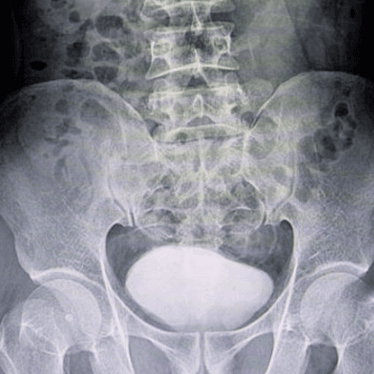

If something goes wrong in this system, your child’s physician may need to take a closer look at their urinary system using a urology test called a voiding cystourethrogram. This test uses fluoroscopy, which is an X-ray that takes pictures in real-time, allowing them to diagnose and treat your child’s condition.

Using the catheter, the radiologist will fill the bladder with contrast material. The contrast temporarily changes the way your child’s urinary system looks on an X-ray, enabling the radiologist to see how their bladder fills and empties.

While your child’s bladder is being filled with contrast, the radiologist will take pictures of your child on their back and both sides using a special X-ray called a fluoroscope camera.